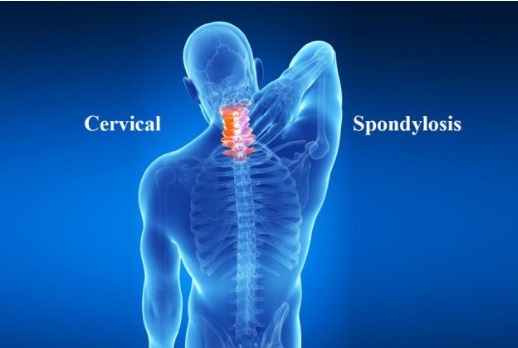

Pain & Spine

Effective treatment for Cervical Spondylitis, Slip Disc, and Sciatica. Regain your mobility and live a pain-free life.

Cervical Spondylitis

गर्दन का दर्द